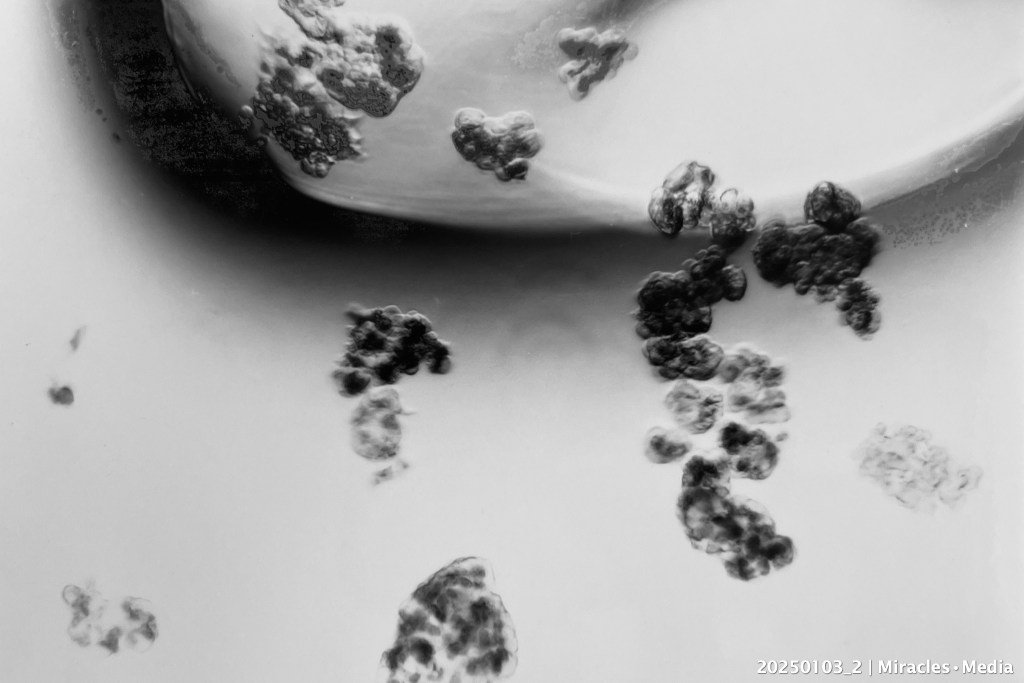

Handpicking Pancreatic Islets • Michel van der Burg • Miracles.Media • 20250103_2 • TakeNode 7988ce39-6777-4db3-82c5-8191acdb13d6

Macro photography (Photo paper print, September 1987, AVC, Leiden University) of the aspiration of isolated canine pancreatic islets, in a suspension still contaminated with exocrine pancreatic fragments, at the tip of a hand blown glass handpicking pipette (custom made at the Leiden University) collected and transferred into tubes for monitoring insulin secretion the first year of pilot work in the Leiden islet laboratory (4).